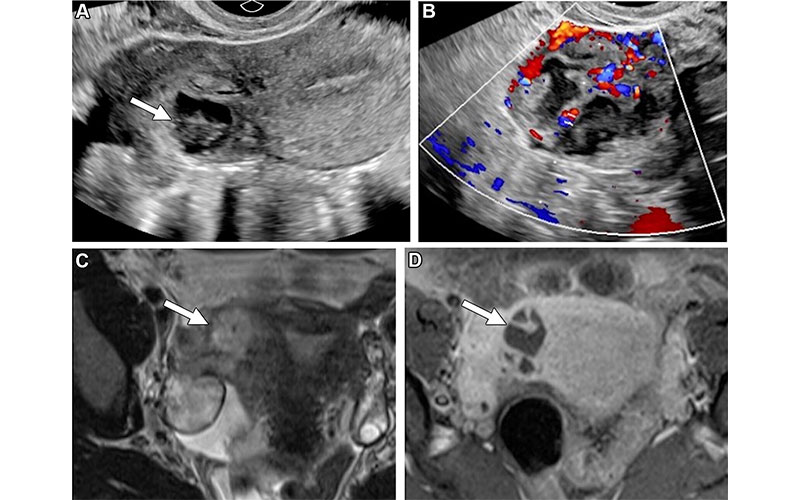

Missed TOA in a 32-year-old woman with right lower quadrant pain. (A) Sagittal transvaginal US image of the right adnexa shows a heterogeneous thick-walled structure with internal anechoic and hypoechoic components (arrow). (B) Color Doppler US image shows internal vascularity. The structure appears inseparable from the uterus and was noted on the radiology report as “likely representing a degenerating exophytic subserosal fibroid.” (C) Subsequent axial T2-weighted MR image shows a right adnexal heterogeneous hyperintense lesion (arrow). (D) Axial fat-suppressed postcontrast T1-weighted MR image shows predominately central nonenhancement within the lesion with thick internal septa (arrow). Findings are most concerning for a right adnexal TOA. Based on the size of the lesion, the patient was given antibiotics. Her mild leukocytosis, which was discovered after imaging, improved.

https://doi.org/10.1148/rg.240101 ©RSNA 2025